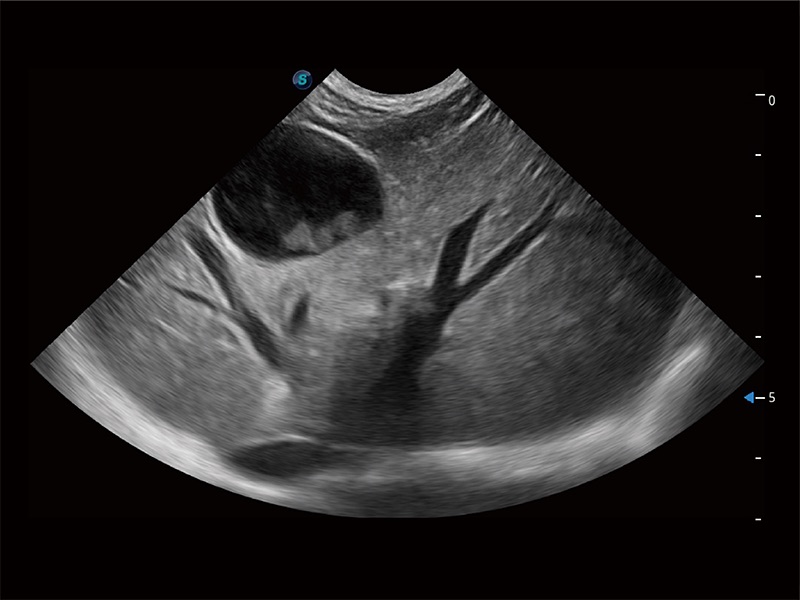

动物是人类最亲密的朋友和最值得信赖的伙伴。milan米兰也一直致力于探索动物专用的超声影像解决方案。全新推出的ProPet系列,是milan米兰在动物超声影像智能化、专业化、精准化的一次跨越式革新。动物不能用言语来表述自己的不适,通过超声影像,ProPet系列搭建了动物医生与不同物种沟通的“桥梁”,为动物医生注入了“治愈之力”。 ProPet 80 是milan米兰匠心打造的一款高端动物专用彩超,采用性能卓越的全新硬件架构,极大提升超声系统的运行效率和数据处理能力,帮助动物医生从容应对日益增多的挑战性病例和日益多样化的临床需求。

高性能和先进的临床应用工具可以为动物医生提供临床信心。ProPet 80 搭载了先进的腹部和浅表应用工具,帮助医生在日常临床实践中发挥前所未有的作用。

ProPet 80 全新的动物超声智能软件和丰富的探头群,为动物医生提供了高清晰度和精细分辨率的图像,无论在宠物、马科、畜牧还是实验室动物等应用中都可以轻松应对,为您的日常工作带来满意的体验。